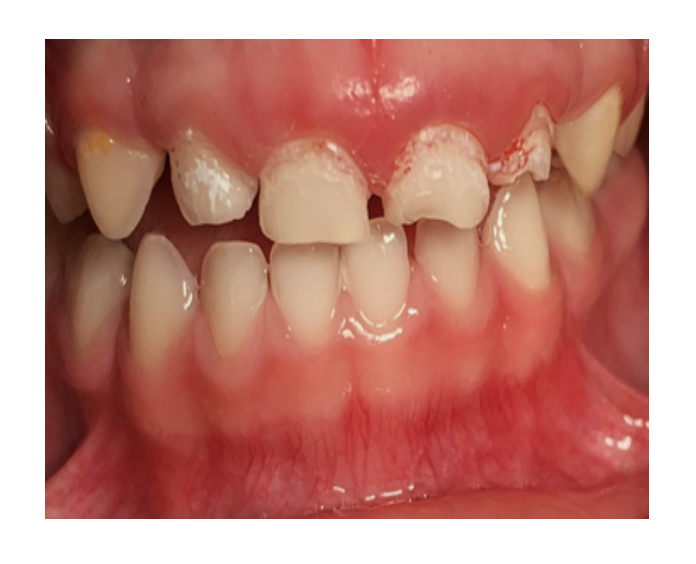

Odontología

infantil